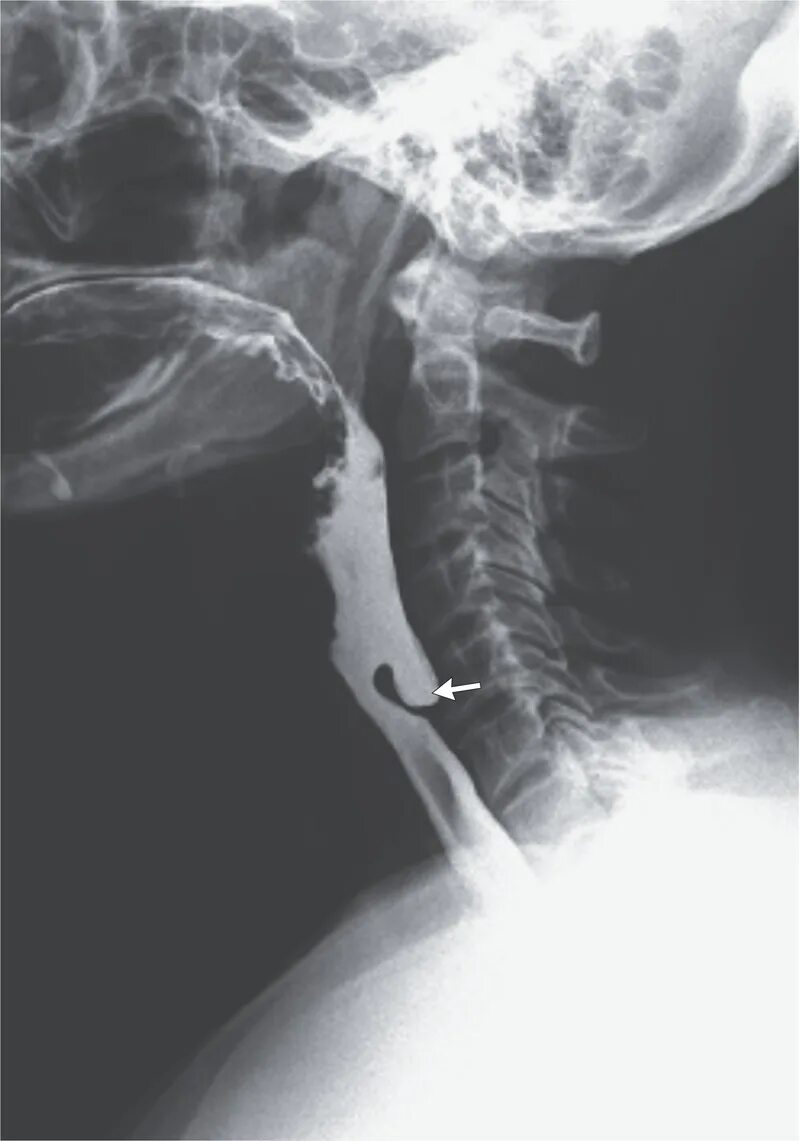

Дивертикул трахеи